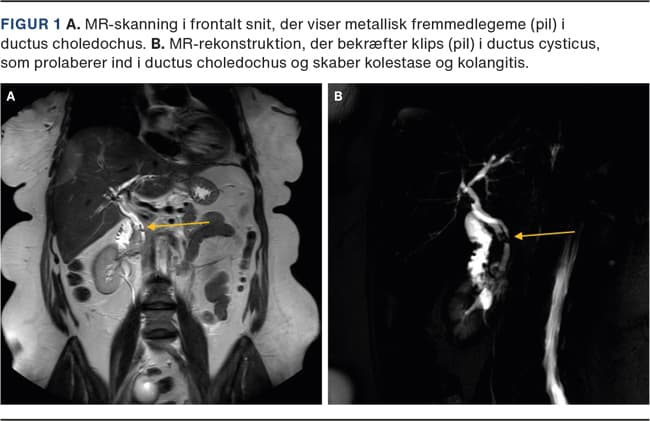

Patienten havde således bakteriæmi med mistænkt abdominalt fokus fra lever, galdeveje eller tarm. CT gav på røntgenkonference mistanke om metallisk fremmedlegeme i ductus choledochus. MR-kolangiopankreatikografi blev foretaget, og denne bekræftede metalklips beliggende i ductus cysticus, hvor den nederste del af klipsen prolaberede ud i den øvre del af ductus choledochus (Figur 1). Patienten fik foretaget akut ERCP, hvor man så fem små stenkonkrementer, der havde samlet sig omkring klipsen. Man ekstraherede klipsen, stenmaterialet og sikrede sufficient afløb. Patienten blev udskrevet velbefindende to dage senere.